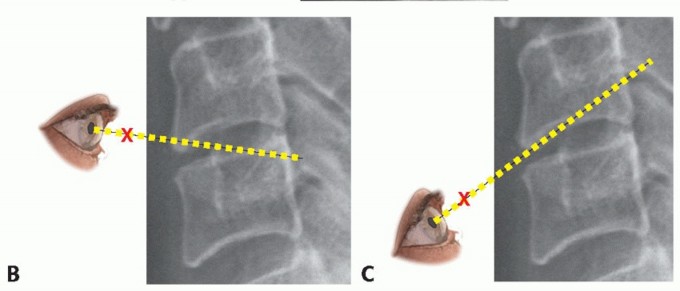

### FIG 3 • MRI and CT scans may provide complementary information in delineating bony versus soft tissue masses. A. On the axial MRI, the compressive lesion has the appearance of a soft disc. B. A CT scan through the same level, however, demonstrates the pathology to be an ossified disc. Similarly, CT scans can help differentiate disc herniations from OPLL. If a high-quality MRI is available but questions remain regarding bony anatomy for the purposes of surgical planning, a noncontrast CT scan provides complementary information (eg, differentiating soft disc versus ossified disc or OPLL) (FIG 3). ## DIFFERENTIAL DIAGNOSIS Cervical radiculopathy Cervical myelopathy Brachial plexus injury Complex regional pain syndrome or reflex sympathetic dystrophy Thoracic outlet syndrome Inflammatory arthropathy Spinal cord tumor Angina Shoulder pathology Peripheral nerve compression (eg, carpal or cubital tunnel syndrome) Diabetic neuropathy Multiple sclerosis Syringomyelia Stroke Guillain-Barré syndrome Normal pressure hydrocephalus Spinal cord tumor ## NONOPERATIVE MANAGEMENT Nonoperative management should be considered as the initial mode of treatment for most patients with radiculopathy. Nonsurgical treatment typically includes physical therapy, traction, pain medication, cervical collars, and epidural injections. It is not clear if nonoperative modalities alter the natural history, but they can provide pain relief while the natural history runs its course. ## SURGICAL MANAGEMENT Surgical intervention is indicated for radiculopathy in patients with persistent symptoms resistant to nonoperative care, progressive weakness, or instability. Common surgical approaches to radiculopathy include ACDF versus posterior laminoforaminotomy.11 ## Preoperative Planning The surgeon should evaluate imaging studies for anatomic variations, such as medial aberrancy of the vertebral artery. To perform a safe but complete and adequate neural decompression, high-quality illumination and magnification are essential. An operating microscope provides illumination and visualization superior to that of loupes and headlights, but either method can be used. Another advantage of the microscope is that the view obtained by the assistant is the same as that of the operating surgeon. If the surgeon chooses to use the microscope, given the smaller field of view, it is imperative to continuously adjust the viewing angle such that a line of sight parallel to the disc space is achieved (FIG 4). If this is not done, the surgeon may inadvertently stray away from the disc space, veer into one vertebral body or the other, and not proceed 3 to the back of the disc space where the decompression needs to occur.

### FIG 4 • Line of sight. When using the microscope, it must be angled properly to provide a parallel view of the disc space to facilitate decompression and endplate preparation. Endplate preparation should proceed in a parallel fashion (dotted red lines) (A) centered on the disc space to achieve a rectangular space for graft insertion. Parallel, wide preparation of the disc space also makes decompression easier to perform and ensures that the decompression is centered on the disc space. B,C. If the line of sight is not maintained, one may err into the vertebral bodies above and below rather than progressing toward the area at the disc level that requires decompression. To achieve parallel surfaces, the inferior endplate of the cephalad vertebra typically requires greater preparation because it is concave. In contrast, the superior endplate of the caudal vertebra is flatter and requires less preparation. C. Proper line of sight is facilitated by removing the anterior lip (arrow, shaded yellow), which allows for better visualization of, and access to, the posterior disc space. ## Positioning The patient is positioned with a bump under the scapula and the occiput on a foam doughnut to prevent pressure necrosis. The amount of extension tolerated preoperatively without excessive pain or neurologic symptoms is recreated. ## Approach A standard Smith-Robinson approach to the anterior cervical spine is used for most cases from C2 to T2. ## TECHNIQUES